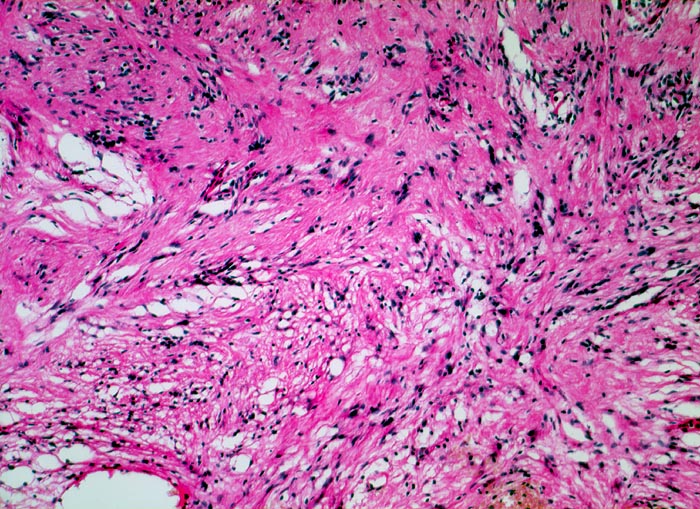

Schwannom: Antoni B Wachstumsmuster

Links oben im Bild kompaktes Wachstumsmuster entsprechend einem Antoni A Muster. Unten im Bild lockere Anordnung der neoplastischen Zellen entsprechend einem Antoni B Muster.

Immunhistochemisch sind die Tumorzellen diffus und stark positiv für S-100 Protein.

Derber abgekapselter Tumor am Nervus ulnaris